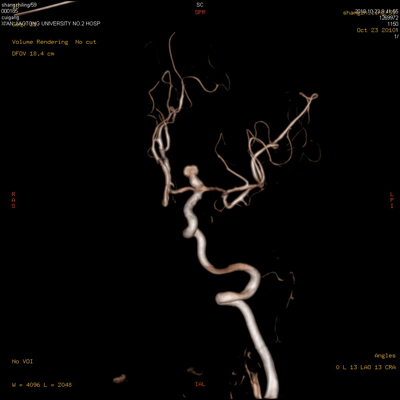

血管仿真内窥镜

脑血管3D成像技术

除了实时DSA,路径图,QVA等常规介入软件外,还将支持Fastspin高速旋转DSA, Bolus chasing下肢血管连续跟踪造影和无缝拼接等高级功能软件,尤其令临床医生振奋的是将支持代表目前血管造影机最高软件水平的3D路径图,Innova3D和InnovaCT。3D路径图与普通路径图相比能更准确地反映血管的真实走向,大大缩短手术时间和难度,对于超选插管等复杂手术具有重大的指导意义。Innova3D可以显示从软组织,骨头和血管的不同断面的图像,一方面可以显示更精确的三维血管图像,而且还可以显示血管与软组织,骨组织之间的关系,可用于血管和其他小部位如脊柱和眼眶的血管和骨头能更精确的观察。而业界独有的InnovaCT更是最高软硬件技术的完美结合,它融合了CT和DSA图像特点,对于疾病诊断和手术计划的制定等方面有很大的用处:如可以用来评估肿瘤的来源, TACE手术血流动力学观察,TACE术后效果判断,肿瘤早期诊断,器官移植的血供分析,脊椎疼痛治疗以及脑神经手术中脑出血诊断等复杂手术。Bolus chasing下肢血管连续跟踪造影和无缝拼接可以实现一次造影就可以全程显示下肢血管。另外其基于3D技术的血管仿真内窥镜技术可以显示血管腔内的结构,为介入诊断治疗提供参考。(影像科 祁晓江/文 张雷 祁晓江/图)